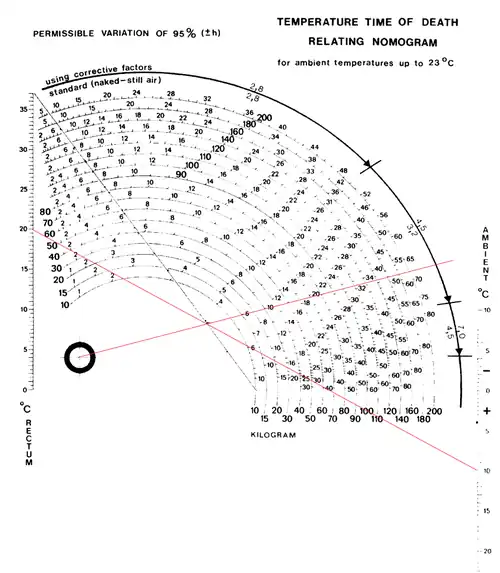

Comme un médecin légiste n'a pas toujours sous la main une calculatrice scientifique pour déterminer t en fonction de T, Claus Hengsse a créé un système d'abaque permettant de déterminer, en fonction de la température du corps, de la température ambiante et de la masse de l'individu, le temps probable de la mort. C'est le Nomogramme de Henssge.

À la valeur trouvée par le Nomogramme de Henssge, il faudra appliquer des facteurs correctifs en tenant compte du fait que l’évolution de la température dépend de nombreux facteurs tels que :

- Des caractéristiques propres au corps : température initiale, âge, éventuellement présence de vêtements…

- Des conditions dépendant du milieu extérieur : présence de vent ou de courants d'air, présence d'humidité, variabilité de la température extérieure.

La méthode la plus pratique pour estimer un délai post-mortem par la méthode thermométrique consiste à utiliser le Nomogramme de Henssge. Mais la modélisation précédente ne joue que pour un corps nu dans un air calme. Il est donc souvent nécessaire de faire intervenir des éléments de corrections qui réduisent ou accélèrent le refroidissement d'un facteur « Cf ». Si « Cf » est supérieur à 1, le corps se refroidit plus lentement. Un facteur Cf inférieur à 1 indique que le corps se refroidira plus vite.

- Corps nu, air calme : Cf = 1,0

- Corps peu habillé, air calme : Cf = 1,1

- Corps habillé modérément, air calme : Cf = 1,2

- Corps habillé chaudement (plus de 4 couches de vêtements), air calme : Cf = 1,4

- Corps très habillé, très couvert, lit : Cf = 2 à 2,4

- Corps nu, air en mouvement : Cf = 0,75

- Corps peu habillé, air en mouvement : Cf = 0,9

- Corps habillé modérément, air en mouvement : Cf = 1,2

- Corps habillé chaudement, air en mouvement : Cf = 1,4

- Corps nu et mouillé, air calme : Cf = 0,5

- Corps peu habillé et vêtements humides, air calme : Cf = 0,8

- Corps habillé modérément et vêtements humides, air calme : Cf = 1,2

- Corps habillé chaudement et vêtements humides, air calme : Cf = 1,2

- Corps nu et mouillé, air en mouvement : Cf = 0,7

- Corps peu habillé et vêtements humides, air en mouvement : Cf = 0,7

- Corps habillé modérément et vêtements humides, air en mouvement : Cf = 0,9

- Corps habillé chaudement et vêtements humides, air en mouvement : Cf = 0,9

- Corps nu dans l'eau stagnante : Cf = 0,5

- Corps peu habillé dans l'eau stagnante : Cf = 0,7

- Corps habillé modérément dans l'eau stagnante : Cf = 0,9

- Corps habillé chaudement dans l'eau stagnante : Cf = 1,0

- Corps nu dans l'eau courante : Cf = 0,35

- Corps peu habillé dans l'eau courante : Cf = 0,5

- Corps habillé modérément dans l'eau courante : Cf = 0,8

- Corps habillé chaudement dans l'eau courante : Cf = 1,0

Il faut cependant prendre conscience que ce calcul ne peut être qu'une estimation. le Nomogramme de Hengsse ne propose pas une durée fixe mais une fourchette d'estimation.

On retrouve un corps dans une mare. Celui-ci pèse 80 kg et sa température rectale est de 20 °C. À l'aide de données météorologiques, on détermine la température moyenne des quinze derniers jours : on obtient, pour la température de l'eau, . Sur le Nomogramme, on lit 22.5 heures pour l'estimation, puis on applique le facteur correctif : étant donné que le corps a été retrouvé dans de l'eau stagnante, il faut multiplier le délai estimé par 0,5.

On obtient donc heures. La fourchette de fiabilité à 95 % est, dans ce cas précis, de + ou - 4,5 heures. ce qui place la date de la mort entre 6.75 heures et 15,75 heures plus tôt.